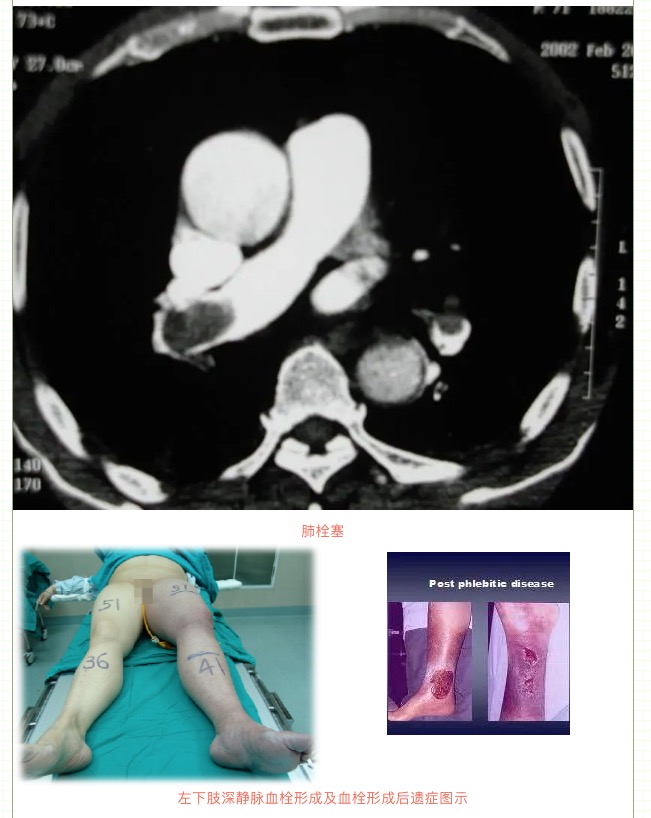

由于下肢靜脈血栓形成導(dǎo)致下肢靜脈血液回流受阻,可能出現(xiàn)單側(cè)腿腫脹、疼痛等表現(xiàn),若出現(xiàn)血栓脫落還可能會導(dǎo)致肺栓塞,嚴(yán)重者可危及生命!如果下肢深靜脈血栓形成沒有接受規(guī)范治療,等血栓機化后,有可能會出現(xiàn)下肢反復(fù)腫脹(晨輕暮重)、皮膚色素沉著、下肢靜脈曲張等表現(xiàn),這就是深靜脈血栓形成后綜合征,也叫血栓后遺癥。

其中,下肢深靜脈血栓形成就是最典型的靜脈阻塞性疾病。由于血栓形成導(dǎo)致下肢靜脈血液回流受阻,出現(xiàn)一側(cè)腿腫、疼痛等表現(xiàn),同時血栓脫落還會導(dǎo)致肺栓塞,危及生命!

因此,一旦發(fā)現(xiàn)下肢深靜脈血栓形成,建議立即就診,在靜脈濾器保護下進行溶栓治療,預(yù)防血栓脫落導(dǎo)致致死性肺栓塞及清除下肢靜脈血栓,防止血栓后遺癥出現(xiàn)。我們的左髂靜脈作為靜脈的重要通道,由于受到動脈和腰椎的壓迫,出現(xiàn)生理性狹窄,因此我們的左下肢相對更容易出現(xiàn)深靜脈血栓、下肢腫脹、下肢靜脈曲張等表現(xiàn),如若出現(xiàn)深靜脈血栓后遺癥或髂靜脈狹窄,必要時需植入髂靜脈支架,避免老爛腿等并發(fā)癥。